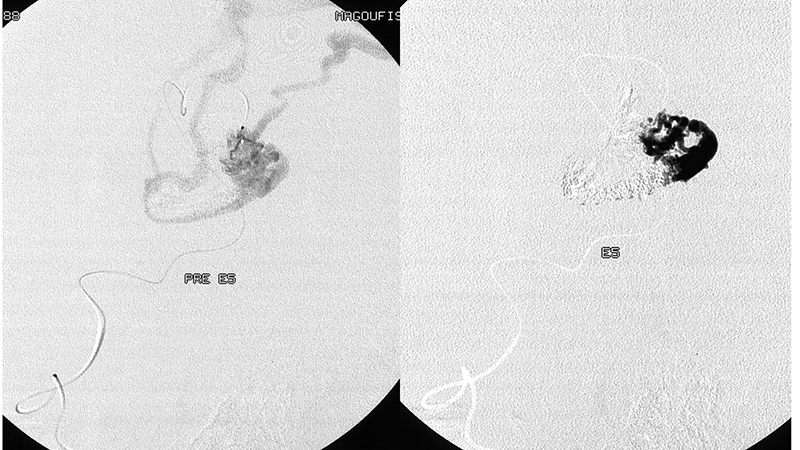

- Υπερεκλεκτικός καθετηριασμός και εμβολισμός από θέση εντός της φωλεάς, με καλή διείσδυση του εμβολικού υλικού στην φωλεά.

- Πλήρης εξάλειψη της δυσπλασίας. Βλέπουμε την αδιάλειπτη συνέχεια του βρεγματικού κλάδου που φαίνεται μετά την απόφραξη της επικοινωνίας(αιχμές κόκκινων βελών).